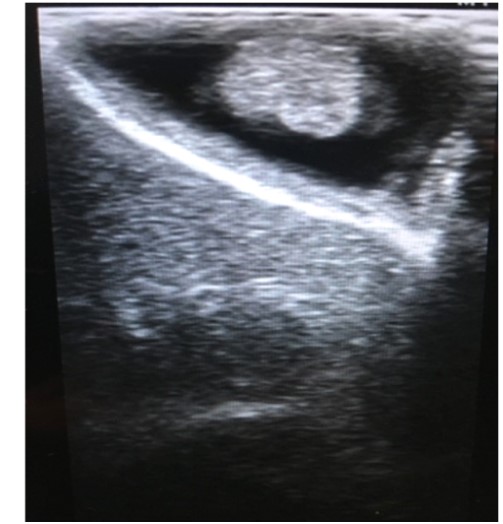

B超:超声是检查胆囊息肉最便捷有效的检查方法,典型的胆囊息肉表现为胆囊壁向腔内凸起的高回声,后方无声影,不随体位改变移动。

胆囊息肉的超声表现